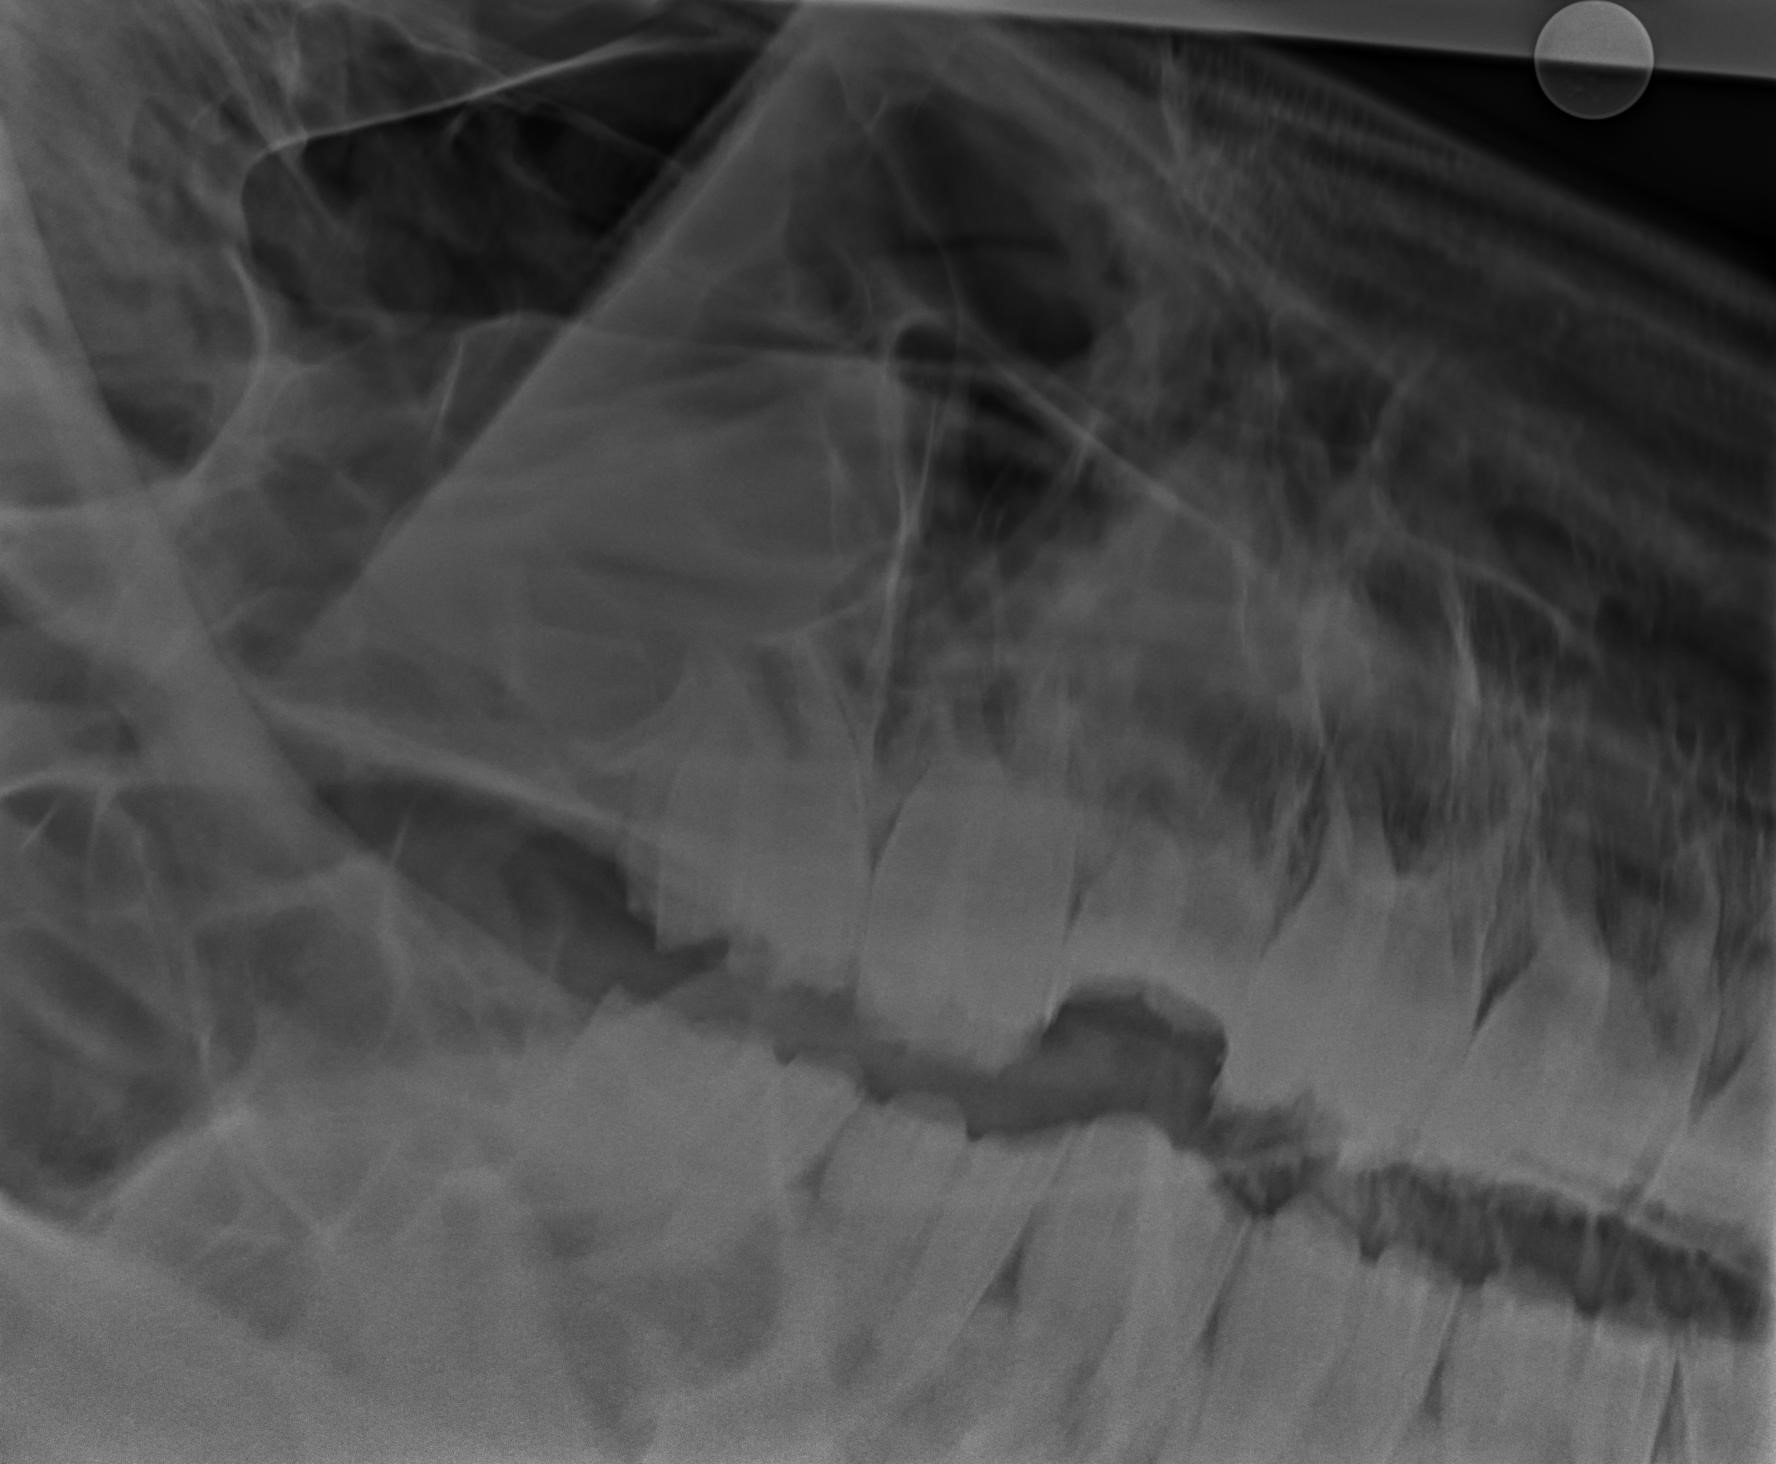

Figure 11 from Paranasal sinus disease in horses. Semantic Scholar Sinus Infection Smell Horse Horses with sinus diseases can also experience swelling in the face or reduced appetite. Swelling on one side of the face,. Sinusitis is an inflammatory condition that often involves excessive nasal discharge. In healthy horses, mucus produced by the lining of the sinuses flows freely through the sinuses and into the nasal passages. Equine sinusitis is the most common disease. Sinus Infection Smell Horse.

Figure 1 from Paranasal sinus disease in horses. Semantic Scholar Sinus Infection Smell Horse A horse with a persistently runny nose and thick discharge from just one nostril is most probably suffering. Sinusitis is an inflammatory condition that often involves excessive nasal discharge. The causes of sinusitis vary but can include dental disease or bacterial infection of the upper respiratory tract. In healthy horses, mucus produced by the lining of the sinuses flows freely. Sinus Infection Smell Horse.